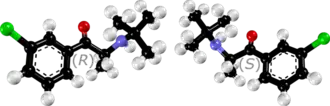

Chemistry

Bupropion is an aminoketone that belongs to the class of substituted cathinones and the more general class of substituted phenethylamines.[32][33] It is also known structurally as 3-chloro-N-tert-butyl-β-keto-α-methylphenethylamine, 3-chloro-N-tert-butyl-β-ketoamphetamine, or 3-chloro-N-tert-butylcathinone. The clinically used bupropion is racemic, which is a mixture of two enantiomers: S-bupropion and R-bupropion. Although the optical isomers of bupropion can be separated, they rapidly racemize under physiological conditions.[2][166]

Bupropion is a small-molecule compound with the molecular formula C13H18ClNO and a molecular weight of 239.74 g/mol.[167][168] It is a highly lipophilic compound,[2] with an experimental log P of 3.6.[167][168] Pharmaceutically, bupropion is used mainly as the hydrochloride salt but also to a lesser extent as the hydrobromide salt.[9][10][169]